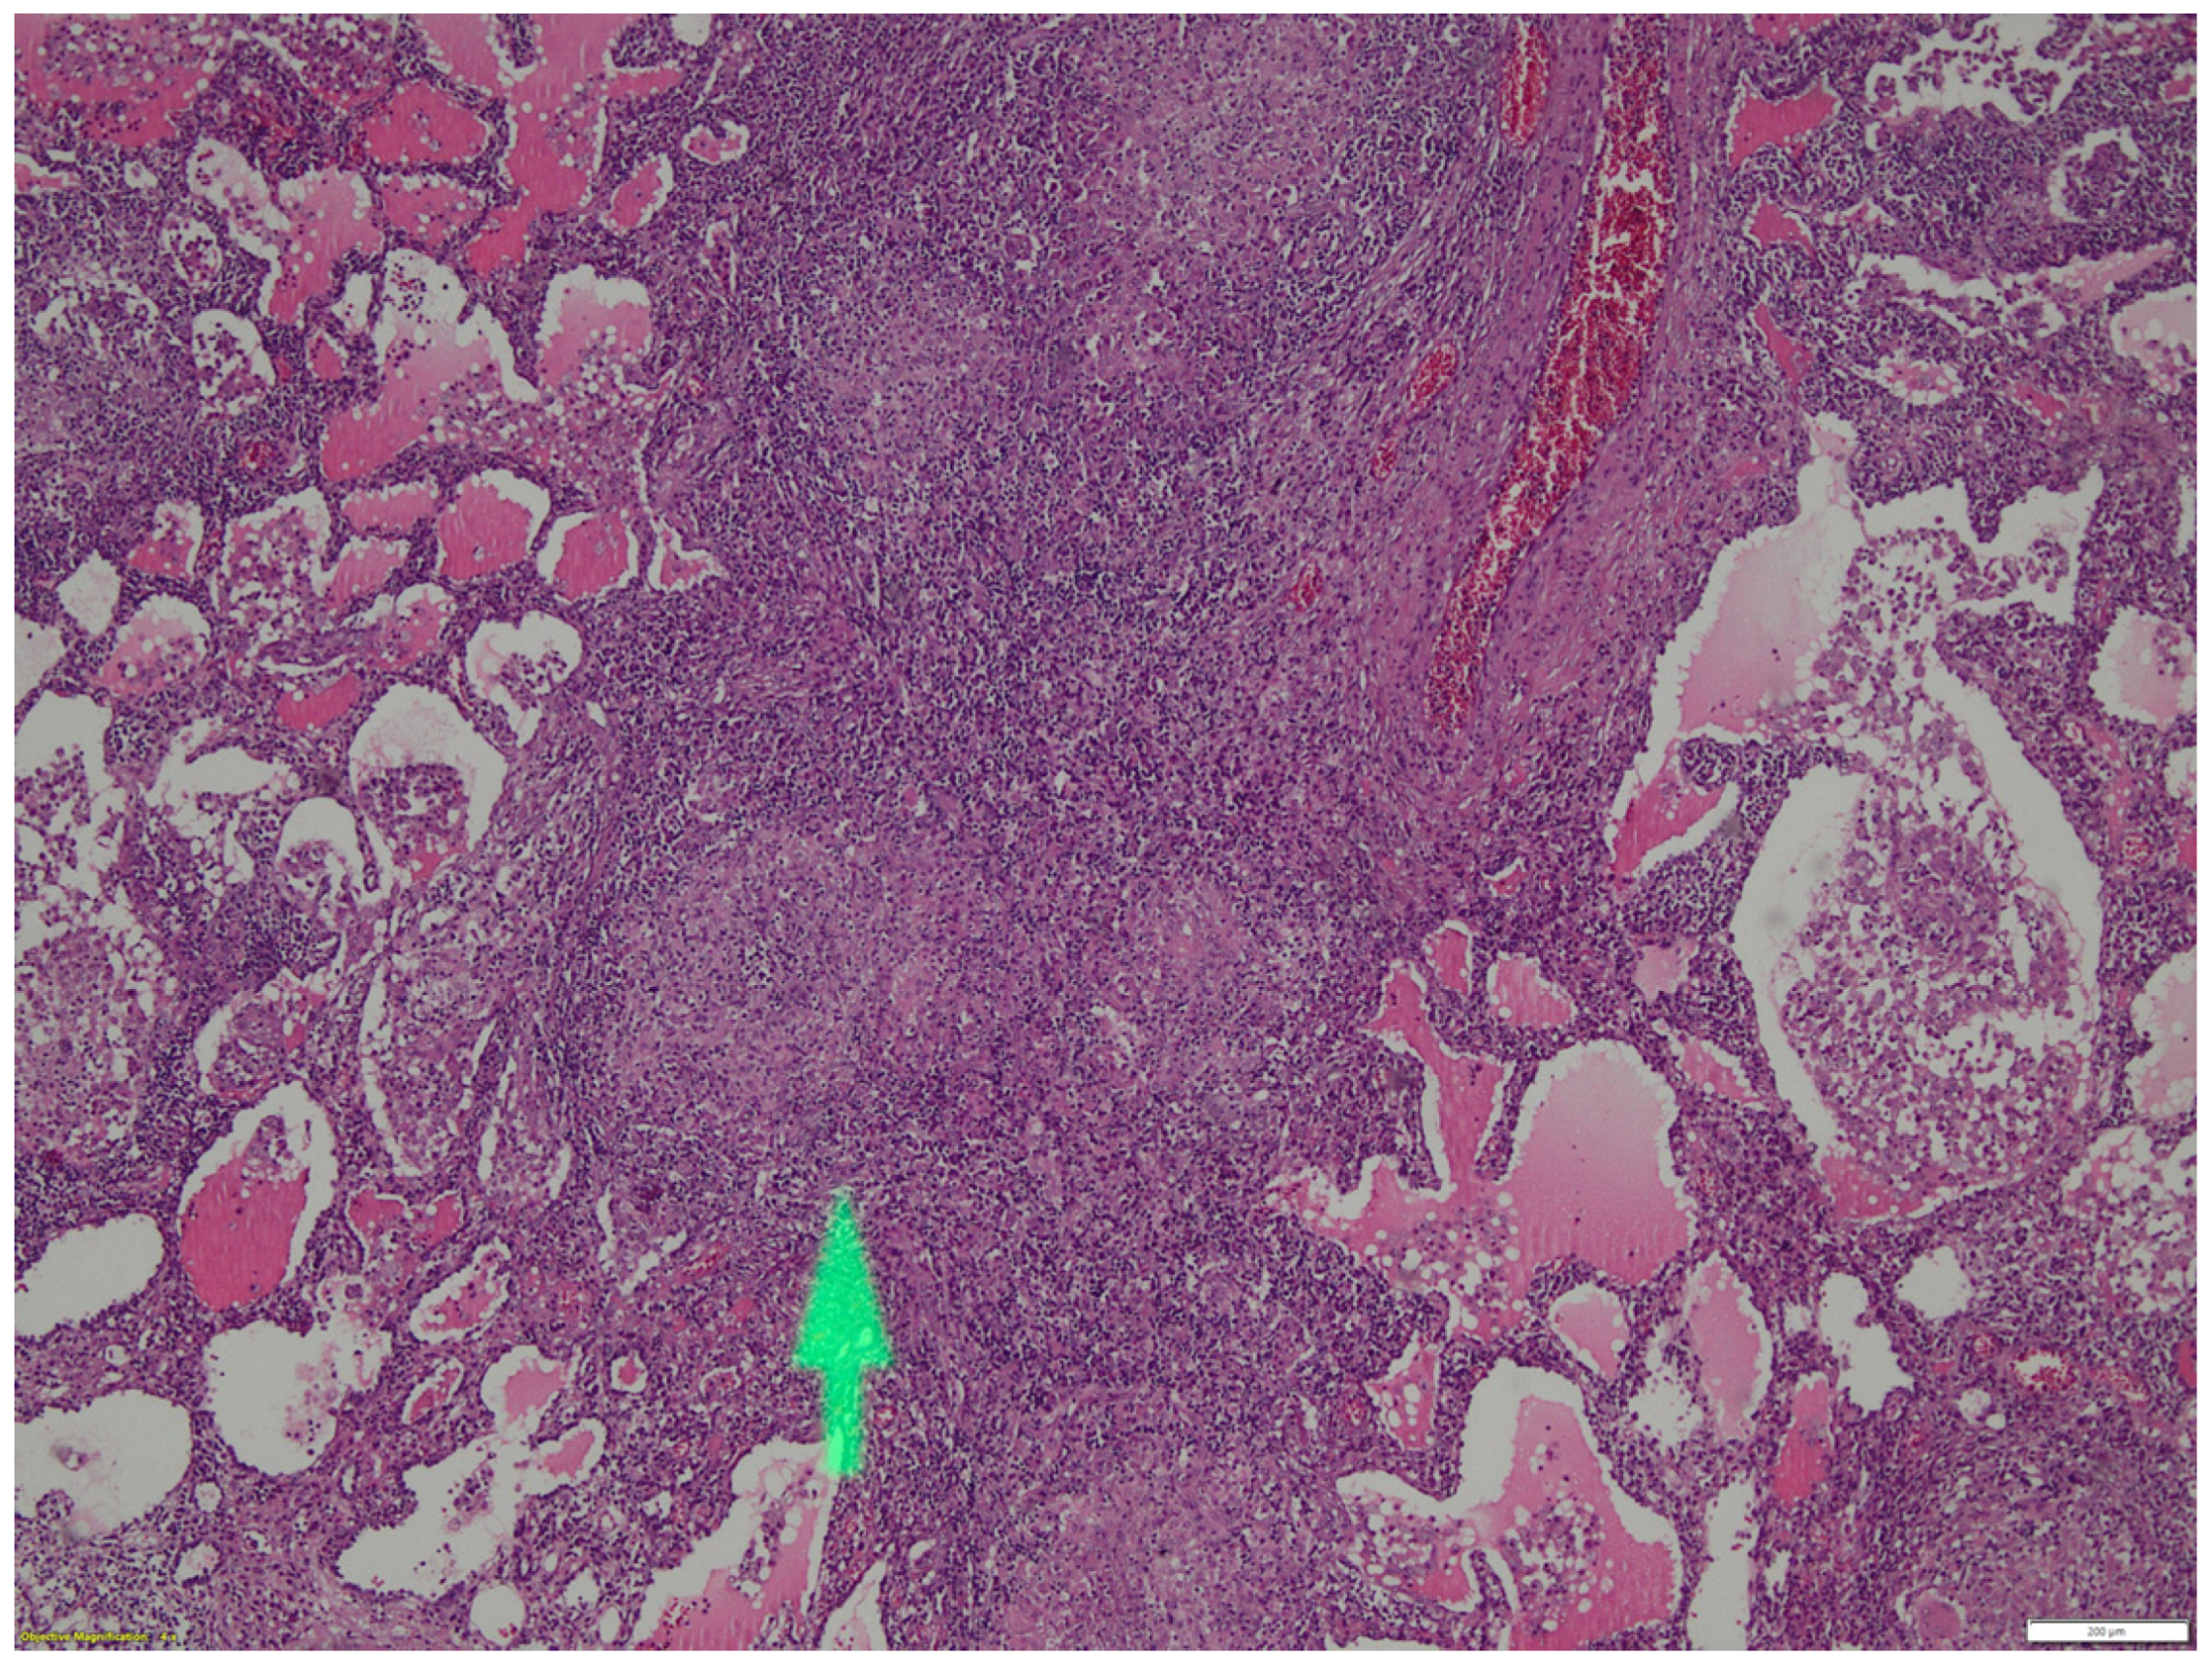

- evidence of non-caseous tissue granulomatous lesions;

- Parenchymal involvement with lymphocytic alveolitis, parenchymal infiltrates and granulomatous bronchioles;

- both are non-caseous granulomatous inflammatory processes,